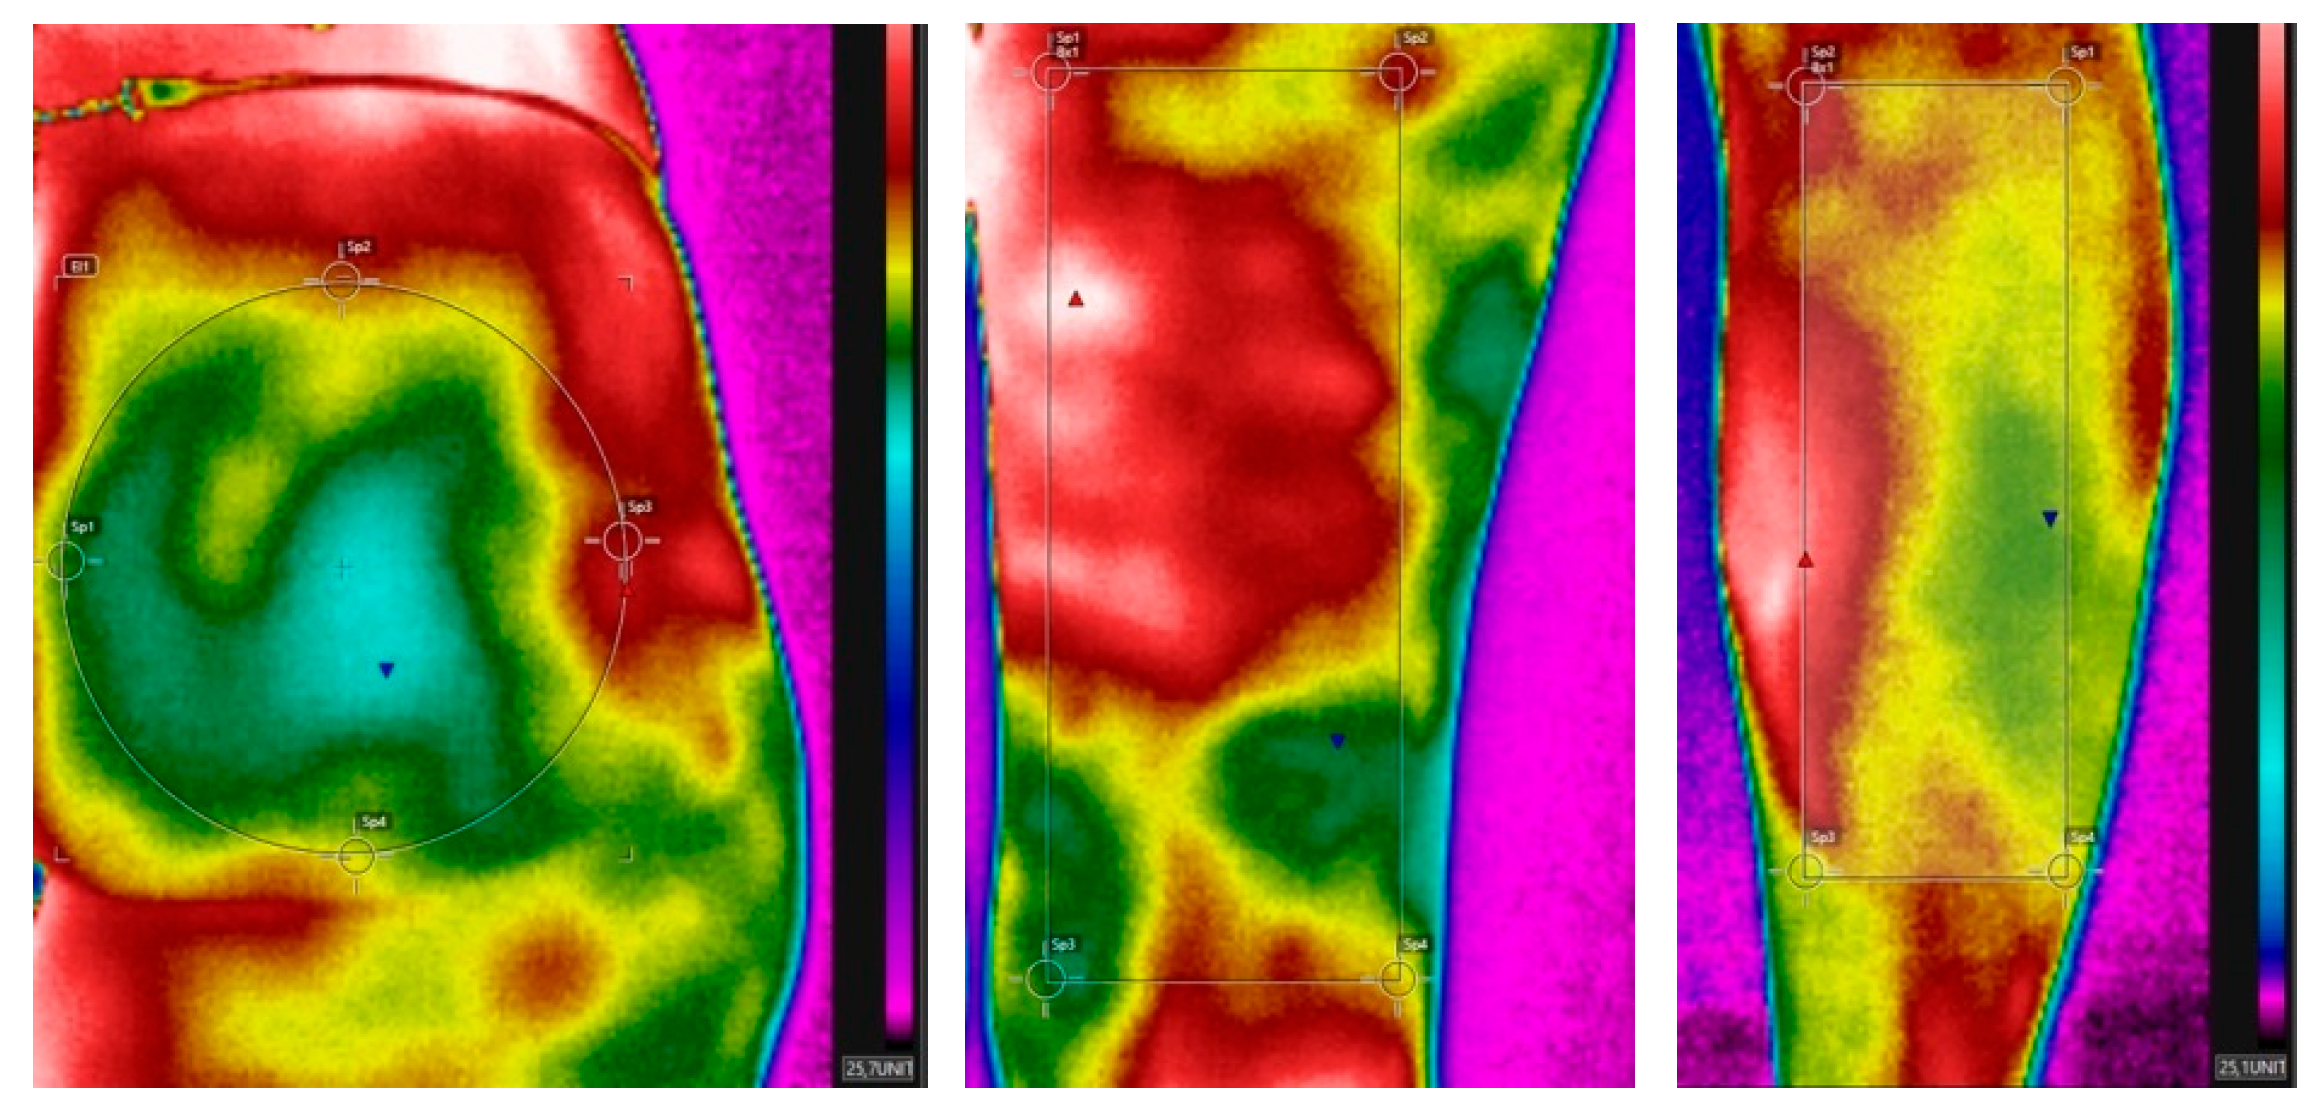

Thermal Camera Results

- Thermal Camera Analysis: Participants wearing microencapsulated garments showed increased skin temperature, indicating improved blood flow and reduced cellulite. Significant interactions were observed in the abdominal region between time and garment group.